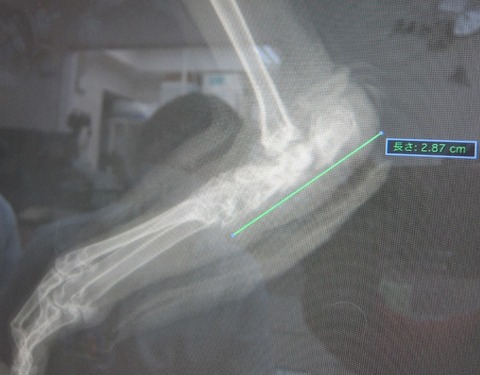

左足患部のレントゲン

本来、かかとの辺り、この部分の骨はこういった状態です。

びっくりしたわ! クロちゃんの骨、全然むちゃくちゃやん! て。

重度だったので潰瘍が骨まで浸食し、骨の中に入りこみ擬化して形成されてる。

…みたいな説明やったと思います(;´Д`)

炎症止めなど投与しているので、侵食されてる骨に痛み等はもうないはず。

表傷が治っても、骨の形成はそのままですが、

骨折しやすいとか、そういった問題を抱えてるわけでもないようです。